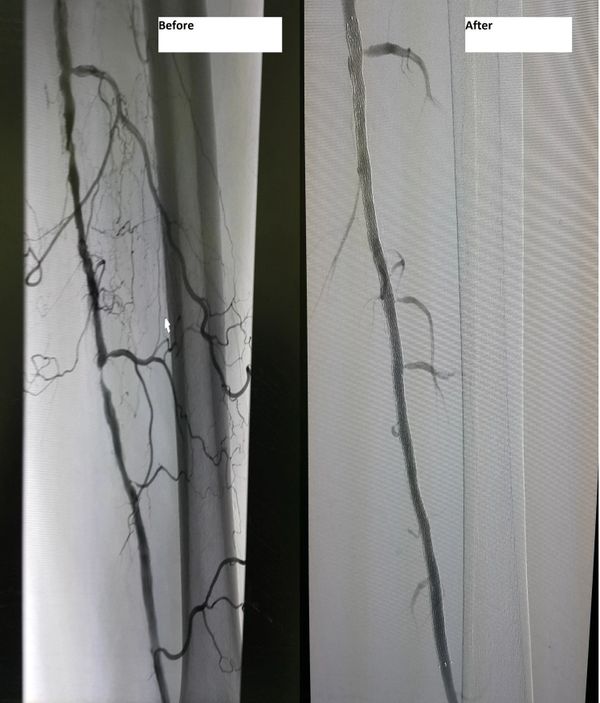

جراح أوعية دموية متخصص في علاج الوحمات الدموية للأطفال - انسداد الشرايين - قدم السكري والغرغرينا -علاج دوالي الساقين بالليزر

استشاري جراحة الأوعية الدموية و القسطرة التداخلية الطرفية